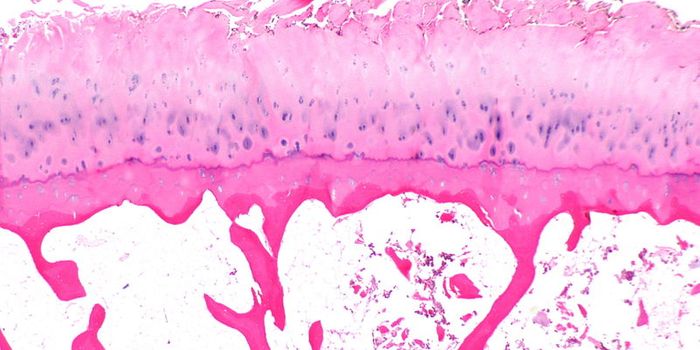

FEB 09, 2024CancerHistopathology describes the process of examining pieces of tissue using a microscope. Light microscopic (LM) exam ...